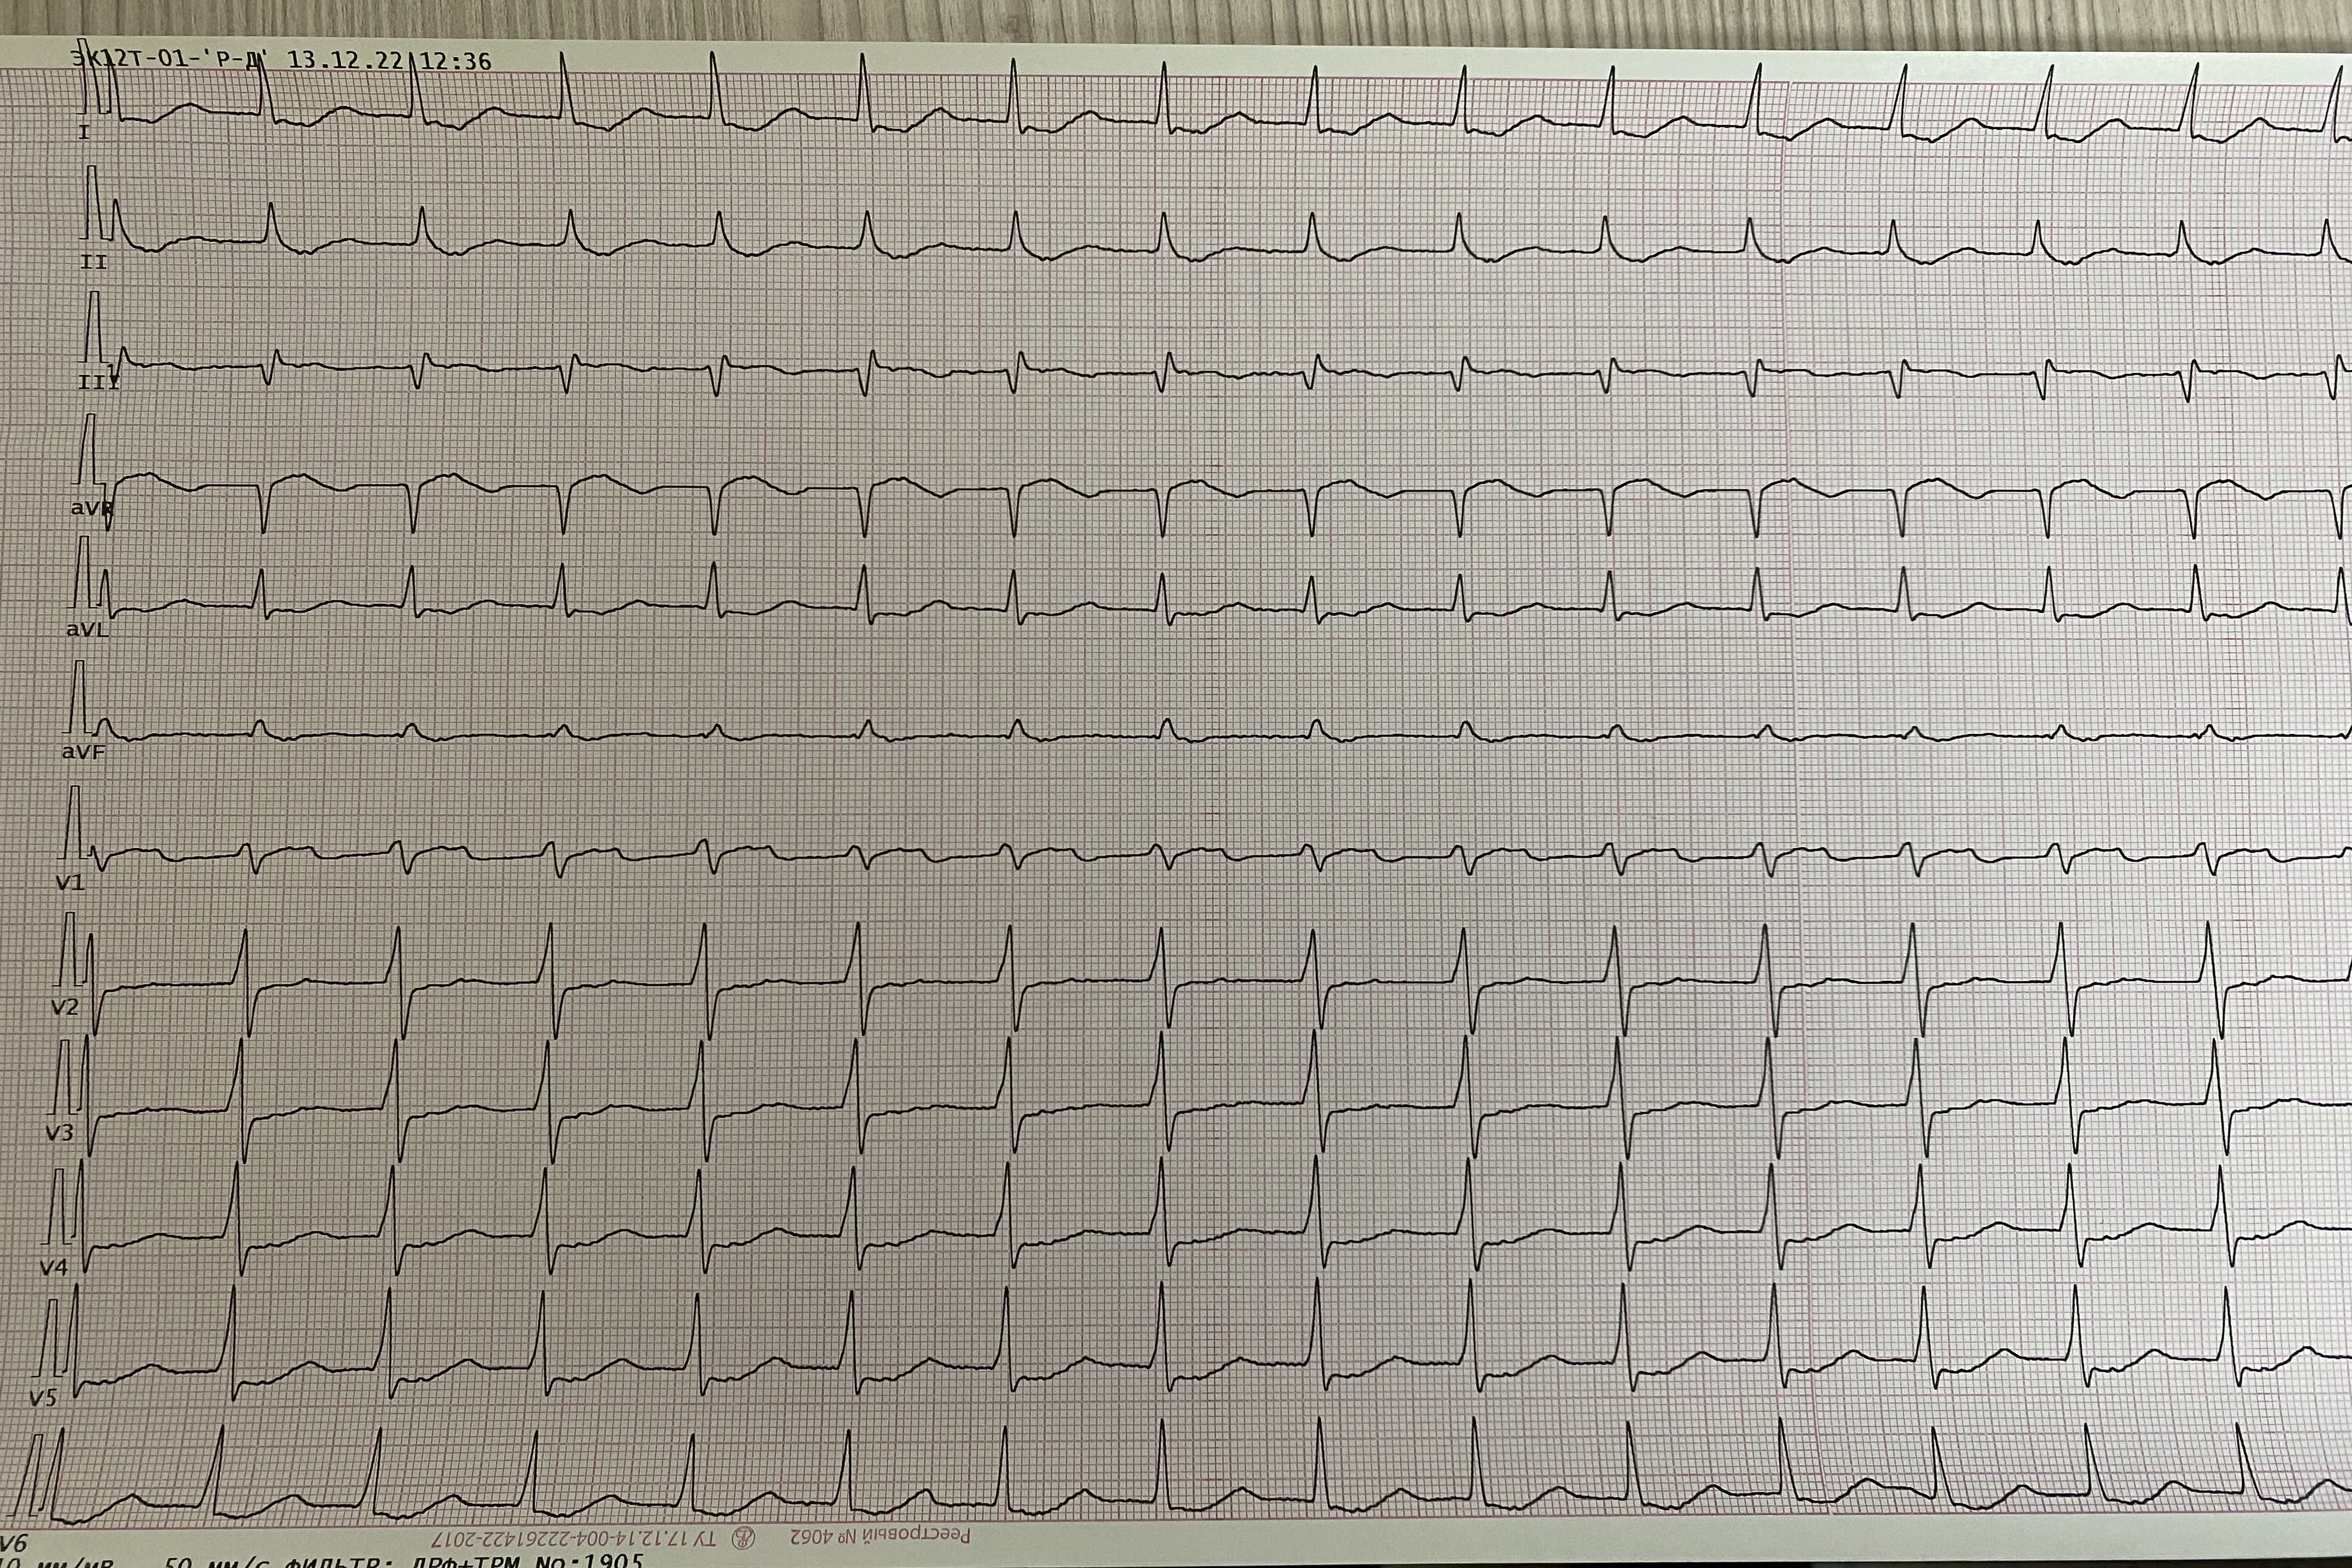

Обсуждалось здесь https://vk.com/club84409679?w=wall-84409679_13416%2Fall

IMG_1405.jpg

IMG_1405.jpg [ 4.29 MiB | Просмотров: 6818 ]